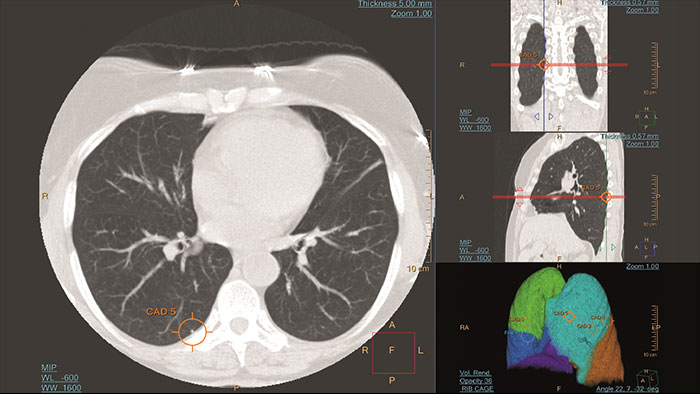

Rely on an artificial second reader Computer-aided detection system for chest multi-slice CT exams

Artificial second reader to support in detection of lesions or nodules which may have been missed.

- detect potentially actionable lung nodules – not just round objects or ROIs - correlate 2D, 3D, and lung maps - register current and prior nodules - calculate nodule changes

*CAD functionality not available for sale in the US.